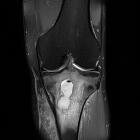

MRI

The “penumbra sign” on magnetic resonance (MR) imaging is useful for discriminating subacute osteomyelitis from other bone lesions. The penumbra sign is a rim lining of an abscess cavity with higher signal intensity than that of the main abscess on T1-weighted images with strongly and rapidly enhance after contrast.